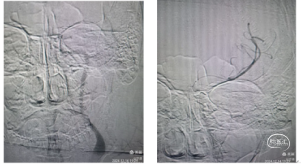

手术过程:术中微造影,颈内动脉血流C5-C6以远未显影。颈内动脉踝奔抽吸滞留血液至C5段,导管不能前行通过。

微导丝艰难通过C5环状迂曲段,到达M1分叉部,微导管冒烟分叉以远显影。

支架取栓:

置入4*20mm Solitaire AB支架,血流初步再通,推注替罗非班15mL后收拢支架尾部负压抽吸取栓导管,回拉支架于导管内。取出约1.5Cm大小硬质血栓。

二次抽吸:通过取栓导管二次接续抽吸清理可能的残余血栓。造影显示全程血流通畅,未见明确血栓逃逸,C5~C6段狭窄约40%。